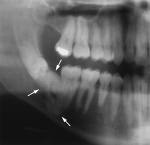

Le cisti

Disodontiasi del terzo molare

Inclusioni dentarie

Patologia dell'eruzione

Odontoma

Ameloblastoma